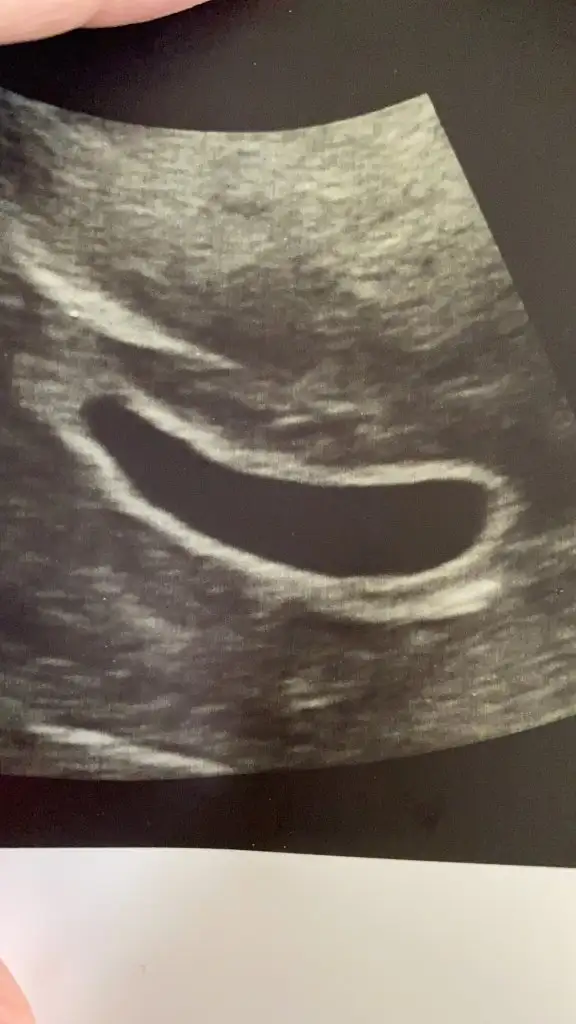

5+3 de gittim bende de yolk yoktu görüntü ekledim vajinal bakıldı

Eklentiler

• 27EE0270-8D01-4A93-8167-CE484A0C715B.webp

27EE0270-8D01-4A93-8167-CE484A0C715B.webp

22,5 KB · Görüntüleme: 213